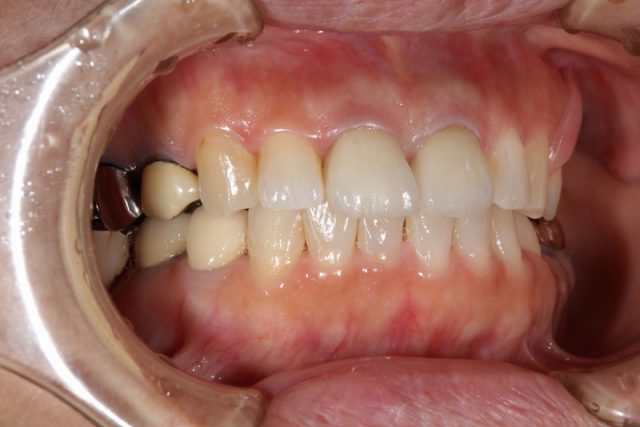

施術後

術後の画像です。前歯の隙間もしっかりと無くなり解消されています。周りの歯との色も自然です。被せ物の付け根はどうですか?被せ物だとはほとんど分からなくなっています。歯の裏面もオールセラミックによる施術では白くなりますのでほとんど被せ物だということは分からなくなります。

見た目も非常に美しくなり、食事後の歯のつまりもほとんど気にならなくなったと非常に喜んでおられました。